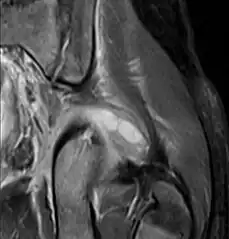

Coronal fat suppressed post contrast image showing a multiloculated bacterial abscess in the left gluteus minimus muscle due to tropical pyomyositis.

Coronal T2 weighted fat suppressed image showing a multiloculated fluid collection in the left gluteal musculature due to tropical pyomositis in a 12-year-old boy.